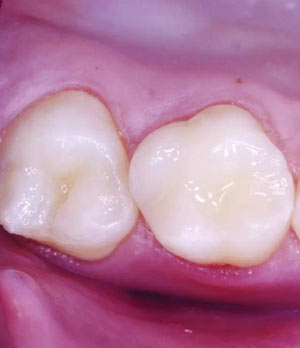

窩溝封閉前后

窩溝封閉后

高質(zhì)量的封閉,對于任何年齡的都有益